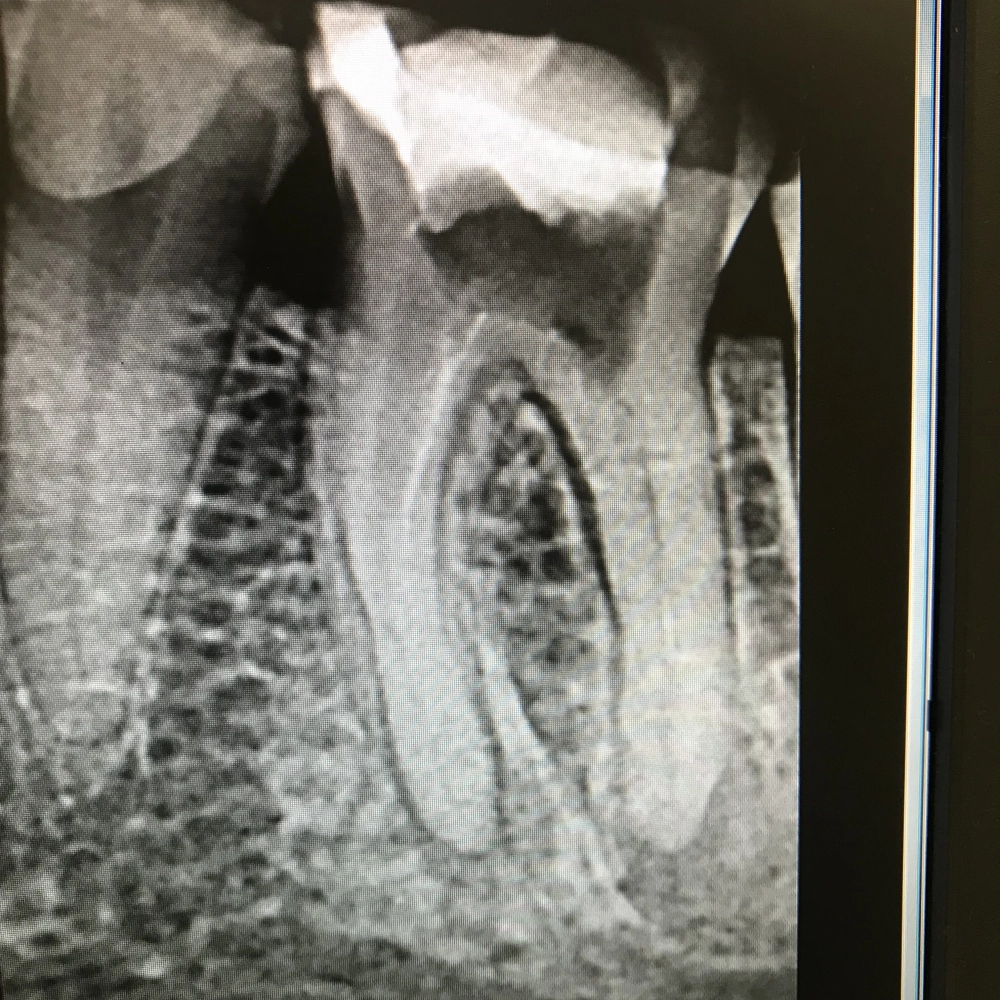

Перелечивание зубов под микроскопом

Проведение повторного эндодонтического лечения,ранее леченного зуба

от 15000 руб.